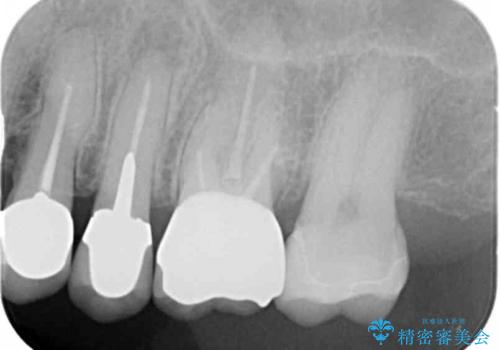

- 銀歯を白くしたいとご希望され、来院された患者様です。

他の歯科医院で銀歯をはずした時に、銀の詰め物が喉に飛んできたことがトラウマとなり、歯科治療が怖くなってしまったとのことでした。

そのためラバーダム(ゴムのシート)をつけることで、詰め物が口腔内に飛んだり破片が飛び散ったりしないよう配慮し治療を行いました。

患者様のご希望により、左上6クラウン、左上7インレーによるセラミック治療を行いました。

再根管治療はご希望されなかったため行っておりません。